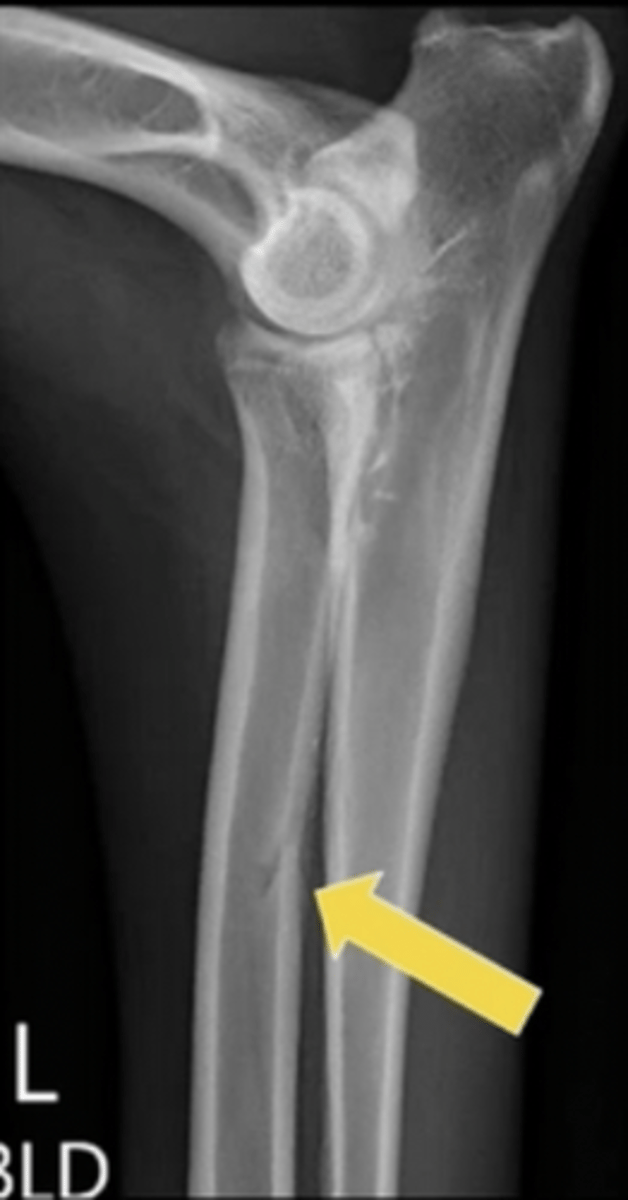

What is the arrow pointing to?

foramen for a nutrient blood vessel

What are the arrows pointing to?